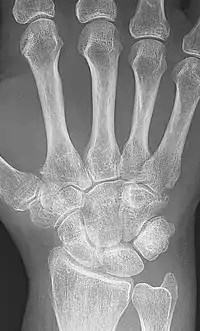

X-ray of the wrist of a woman with rheumatoid arthritis, showing unaffected carpal bones in the left image, and ankylosing fusion of the carpal bones 8 years later in the right image.